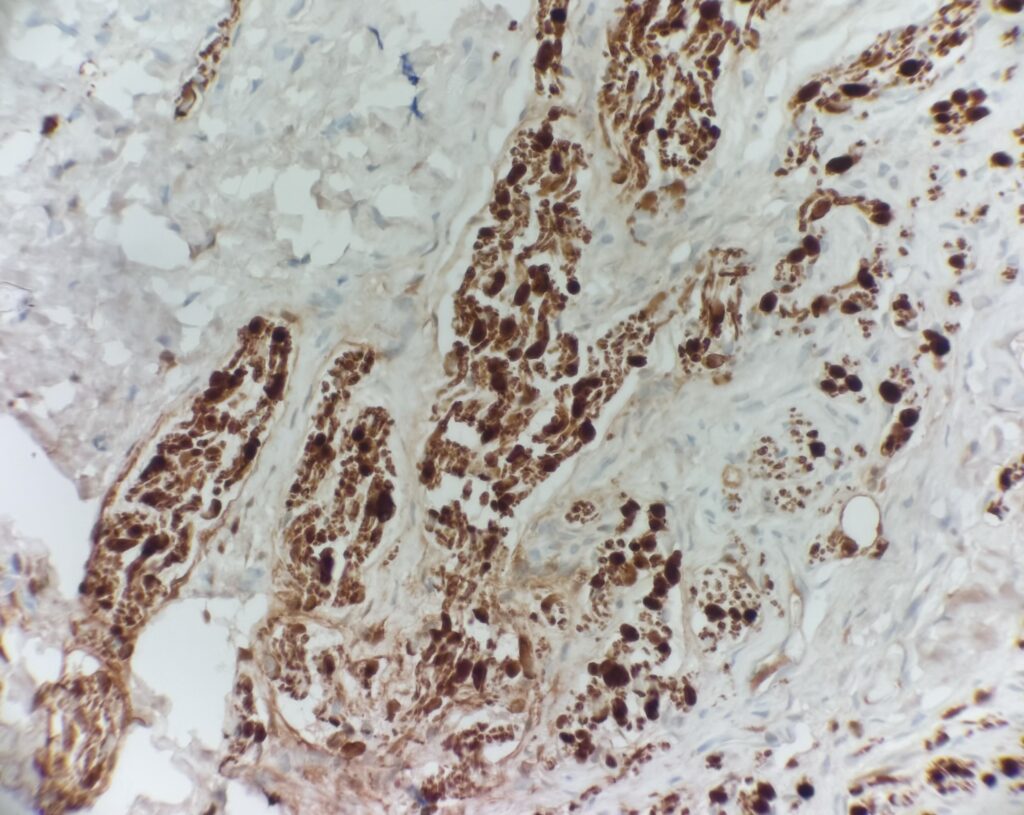

Histology:

Traumatic neuroma – Benign proliferation of nerve bundles. Histologic sections show haphazard proliferation of neural structures at the base of the lesion (highlighted on S-100 stain).